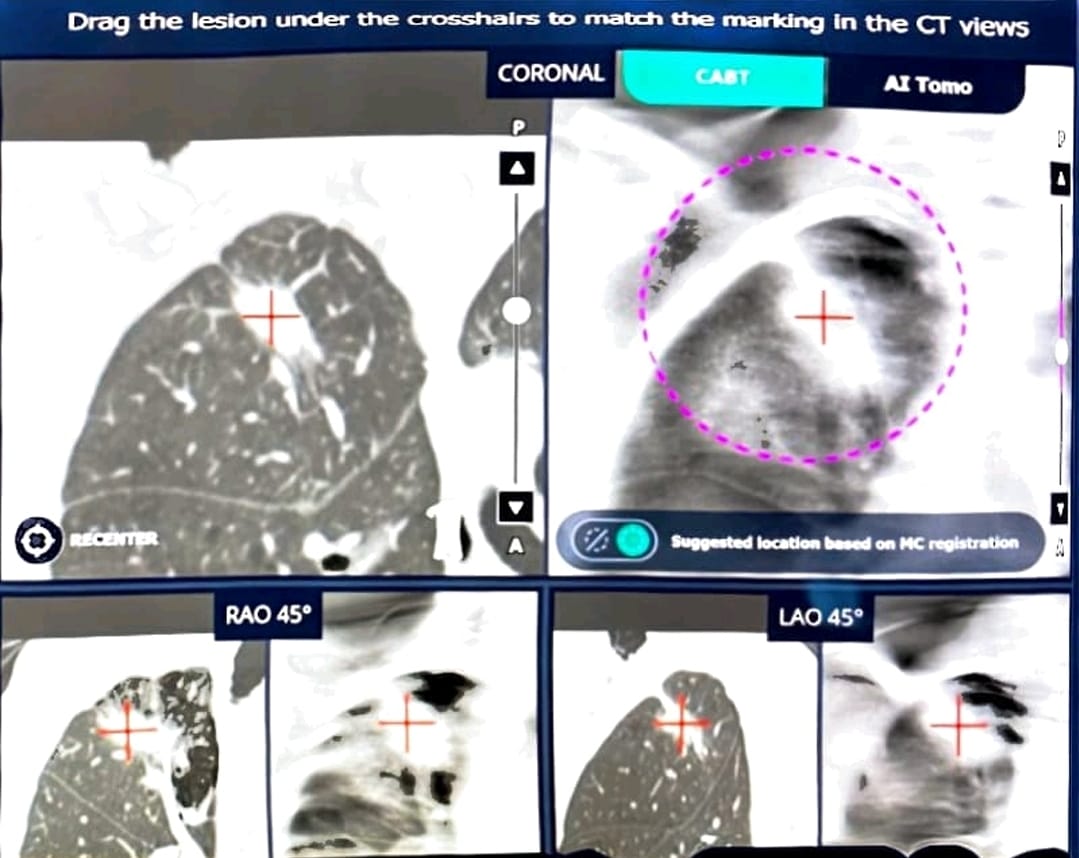

(n. 57/2026) L’intelligenza artificiale approda nell’Unità operativa di Pneumologia del Ca’ Foncello. Dopo una prima fase di prova, la “fluoroscopia aumentata” è arrivata, infatti, nel reparto diretto dalla dr.ssa Micaela Romagnoli in via definitiva. Il sistema acquisito, sviluppato negli Stati Uniti, grazie all’AI permette, durante la broncoscopia, di vedere in 3D la posizione dello strumento rispetto alla lesione nel polmone, aiutando il medico a prelevare il tessuto nel punto corretto.

L’équipe di Pneumologia aveva già eseguito nel 2024, per la prima volta in un ospedale pubblico del Veneto, alcune complesse procedure broncoscopiche con sistema di guida con “fluoroscopia aumentata” in casi di sospetta neoplasia polmonare. “Grazie all’utilizzo di questa nuova tecnologia – spiega il primario - è possibile ottenere un adeguato campionamento istologico con la sicurezza di essere all’interno della lesione durante i prelievi in casi di noduli sospetti per tumore del polmone, non altrimenti raggiungibili né per via transtoracica né per via broncoscopica con i tradizionali sistemi di guida come, ad esempio, l’ecografia radiale endobronchiale abbinata alla fluoroscopia classica già in utilizzo a Treviso.

“Campionare per via broncoscopica il tessuto polmonare di un sospetto tumore – sottolinea  Romagnoli - non è solo una questione di modalità di campionamento ma è, soprattutto, questione di ben ‘indirizzare’ il campionamento stesso, che può risultare difficile per la posizione molto periferica di alcuni noduli, oltre che per la mancanza di una ricostruzione dell’immagine della TAC torace in 3D che possa assicurare allo pneumologo broncoscopista di essere correttamente all’interno della lesione al momento del prelievo istologico. La corretta diagnosi istologica broncoscopica eseguita con i moderni sofisticati sistemi di guida permette di effettuare, con maggior sicurezza, interventi chirurgici su pazienti con diagnosi di tumore del polmone già accertata e confermata”.